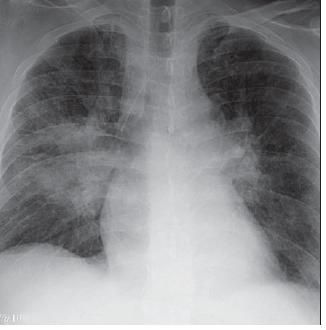

Five days after the initiation of sulfasalazine therapy, he had a low-grade fever, subacute breathlessness, and mild hypoxemia without cough or hemoptysis. A chest radiograph taken 11 days after sulfasalazine treatment was started demonstrated bilateral infiltrates with right lung perihilar consolidation, early left mid-lung zone infiltrate, and bilateral perihilar interstitial prominence (Figure 1). Pulmonary consultation was requested.

Figure 1 – Bilateralinfiltrates with right lung perihilar consolidation can be seen in the chest radiograph taken 11 days after the initiation of sulfasalazine therapy. Other radiographic findings include a left mid-lung zone infiltrate and bilateral perihilar interstitial prominence.